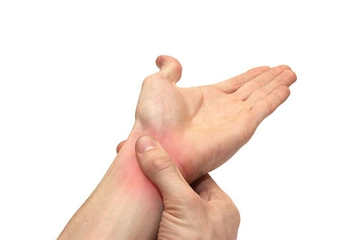

El bileği burkulması, genellikle bağ dokularının zorlanması veya yırtılması sonucu oluşur ve belirtileri kişiden kişiye değişiklik gösterebilir. Kızarma, ağrı, şişme ve bölgedeki sıcaklık artışı en yaygın belirtilerdir. Bu belirtiler genellikle burkulmanın şiddetine bağlı olarak birkaç gün ile birkaç hafta arasında sürebilir.

Eğer burkulma hafifse, belirtiler birkaç gün içinde azalarak geçebilir. Ancak, orta veya şiddetli burkulmalarda belirtiler daha uzun sürebilir. Şişlik ve ağrı genellikle ilk 48 saat içinde en yoğun seviyede olur ve zamanla azalır. Yine de, eğer belirtiler 1-2 hafta içinde geçmezse, bu bir sağlık sorununun işareti olabilir.

Ağrınız şiddetliyse, günlük aktivitelerinizi etkiliyorsa veya el bileğinizin işlevselliğinde belirgin bir azalma varsa, bir doktora başvurmanız önemlidir. Ayrıca, eğer burkulma sonrası el bileğinizde aşırı şişlik, morarma veya hareket kısıtlılığı gibi durumlar söz konusuysa, bir sağlık profesyoneline görünmekte fayda vardır.